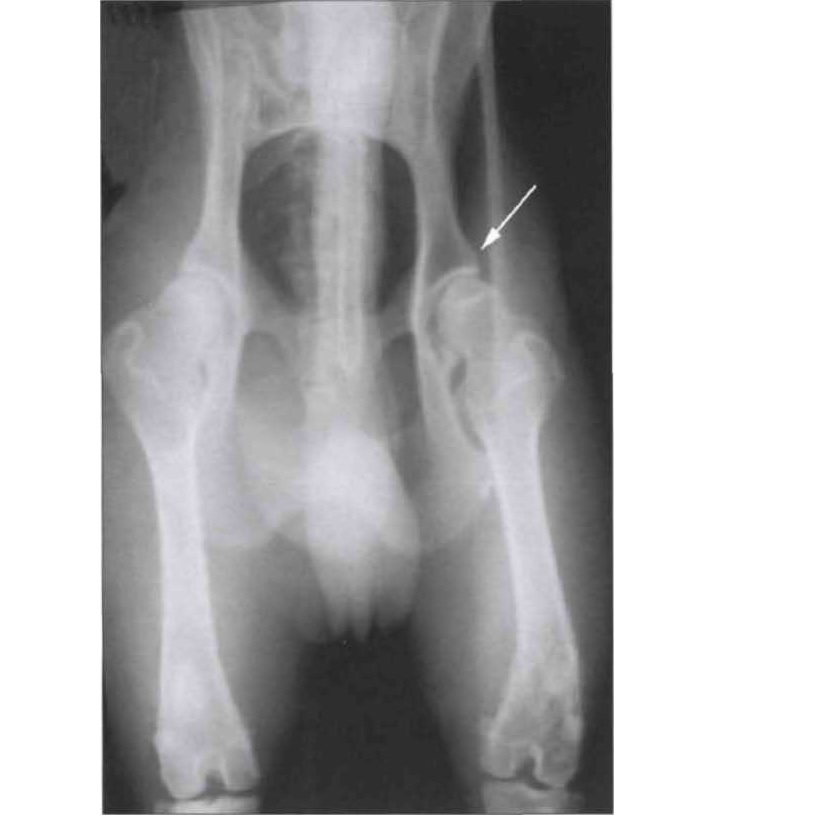

Ньюфаундленд, 7 лет (!) резко захромал несколько дней назад, после обследования выявлено полное разрушение сустава вследствие дисплазии.

В этом случае, к сожалению, поможет только удаление головки бедра или замена сустава с длительным реабилитационным периодом.

Рентген ТБС собаки. Двусторонняя дисплазия, артроз